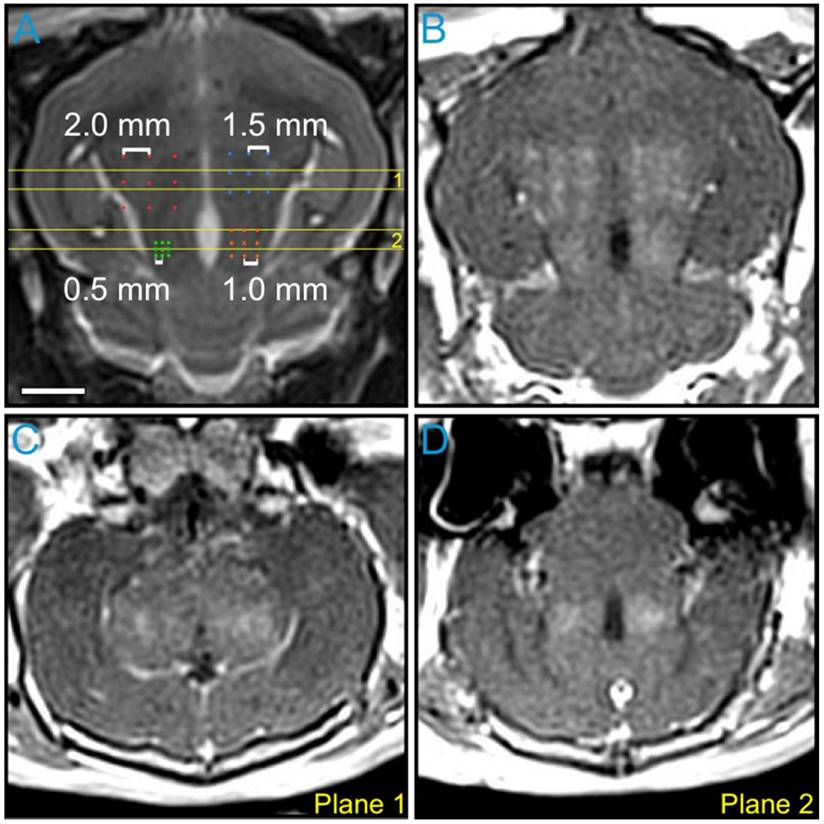

The impact of point spacing for multi-point BBB opening exposures at a transmit frequency of 612 kHz was investigated in the first rabbit of the pilot group (Figure 4). Four multi-point grids with point spacings ranging from 0.5-2.0 mm were arranged in the same axial plane (Figure 4A) and sonicated at each grid's respective 75% target level. Post-sonication CE-T1w MRI scans depicted increased BBB permeability levels relative to baseline (i.e., pre-sonication) within each of the targeted regions (Figure 4B-D). Visible drops in image intensity between grid points were observed for spacings of 1.5 mm and above, whereas a more uniform enhancement pattern was observed for spacings of 1.0 mm and below (Figure 4B and Figure S4A). This process was repeated in a more superior, non-overlapping axial plane in the same animal. Based on these data, a point spacing of 1.0 mm was chosen for all subsequent multi-point exposures, as it provided the best compromise between the BBB opening volume (Figure S4B) and the enhancement uniformity (Figure S4C).

Figure 4

Variable point spacing during multi-point exposures via electronic steering. Variable point spacing during multi-point BBB opening exposures (f0 = 612 kHz) was investigated in the first animal from the pilot group. Four 3 × 3 grids were sonicated with point-to-point spacings of 0.5 mm (green), 1.0 mm (orange), 1.5 mm (blue), and 2.0 mm (red). Each grid was sonicated at its respective 75% target level, based on calibration sonications carried out at the central grid point ('×' symbols). (A) Target locations overlaid on an axial T2w MR image. (B) Axial CE-T1w MR image depicting BBB opening within each targeted volume. Coronal CE-T1w MR images intersecting the two (C) anterior- and (D) posterior-most grids. The coronal slice volumes are indicated on the axial T2w MR image in (A) by the horizontal yellow lines (Planes 1 and 2). The sonication direction is out of the page in (A-B) and bottom-to-top in (C-D). Scale bar indicates 5 mm.

Theranostics Image